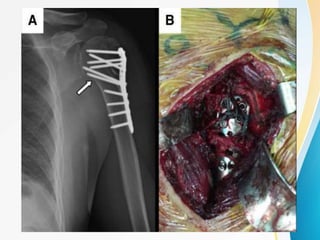

4-PART MARKED DISPLACEMENT, VARUS

MALALIGNMENT , FRACTURE DISLOCATION :

4 STEPS

• Incision through deltopectoral approach

• Reduction and preliminary fixation

• Plate fixation

• Rotator cuff tendon suturing to the plate .

STEP 2 :

• Place rotator cuff sutures

• supraspinatus ,infraspinatus and subscapularis

• pull them and head split reduced using periostome

• preliminary k-wires are inserted into head through

gt

• shaft of humerus is fixed to the head using k-wires

placed anteriorly

• temporary reduction achieved

STEP 3 :

• Attach plate to humeral shaft

• and fix the plate by passing a compression screw on the

shaft

• now make drill holes through drill sleeves into the humeral

head

• drill the near cortex only ,woodpecker drilling technique

• minimum of 5 screws placed

• check screw size under c-arm

• calcar screws are essential in all varus displaced fractures

STEP 4 :

• if needed , a lag screw can be inserted into

lesser tuberosity .

• additional shaft screws are inserted (bicortical

screws)

• Rotator cuff tendon sutures are placed through

the suture holes and secured { ↑ stability }